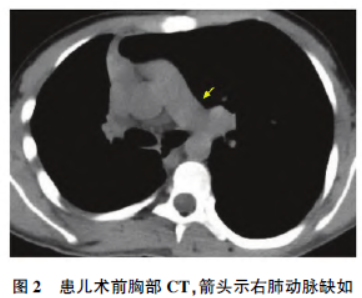

胸部CT(图2)示右侧胸廓较对侧缩小;右肺胸膜下肺大泡、肺气肿

。肺功能示限制性通气功能障碍,用力肺活量(forcedvital capacity, FVC)2. 69 L 占预计值53%,第1 秒用力呼气量( forced expiratory value in 1 second,FEV1)2. 18 L 占预计值52%,FEV1/ FVC 为81%。拟在全身麻醉下行后路脊柱侧凸截骨矫形、内固定、植骨融合术。术前评估ASA 分级Ⅲ级,心功能分级Ⅰ~Ⅱ级。